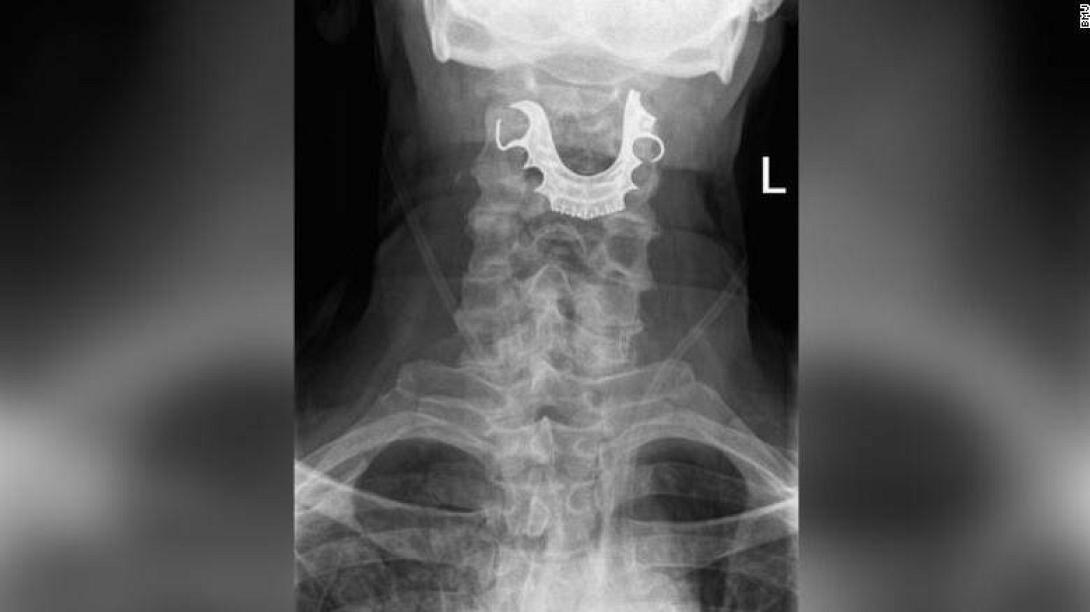

Τελικά, μέσω ακτινογραφιών οι γιατροί εντόπισαν ένα ημικυκλικό αντικείμενο στις φωνητικές του χορδές, το οποίο προκαλούσε τη δημιουργία εσωτερικών φουσκαλών και πρήξιμο.